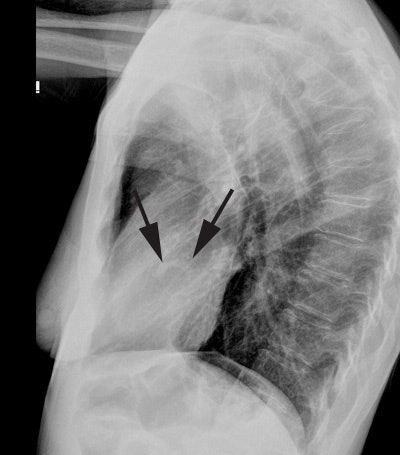

Case 2: Heavily calcified aortic valve

The lateral CXR below revealed dense calcifications in the region of the aortic valve (black arrows). When seen on plain film, the findings is very suggestive of aortic stenosis. CT imaging in this same patient also revealed very dense aortic valve calcifications.